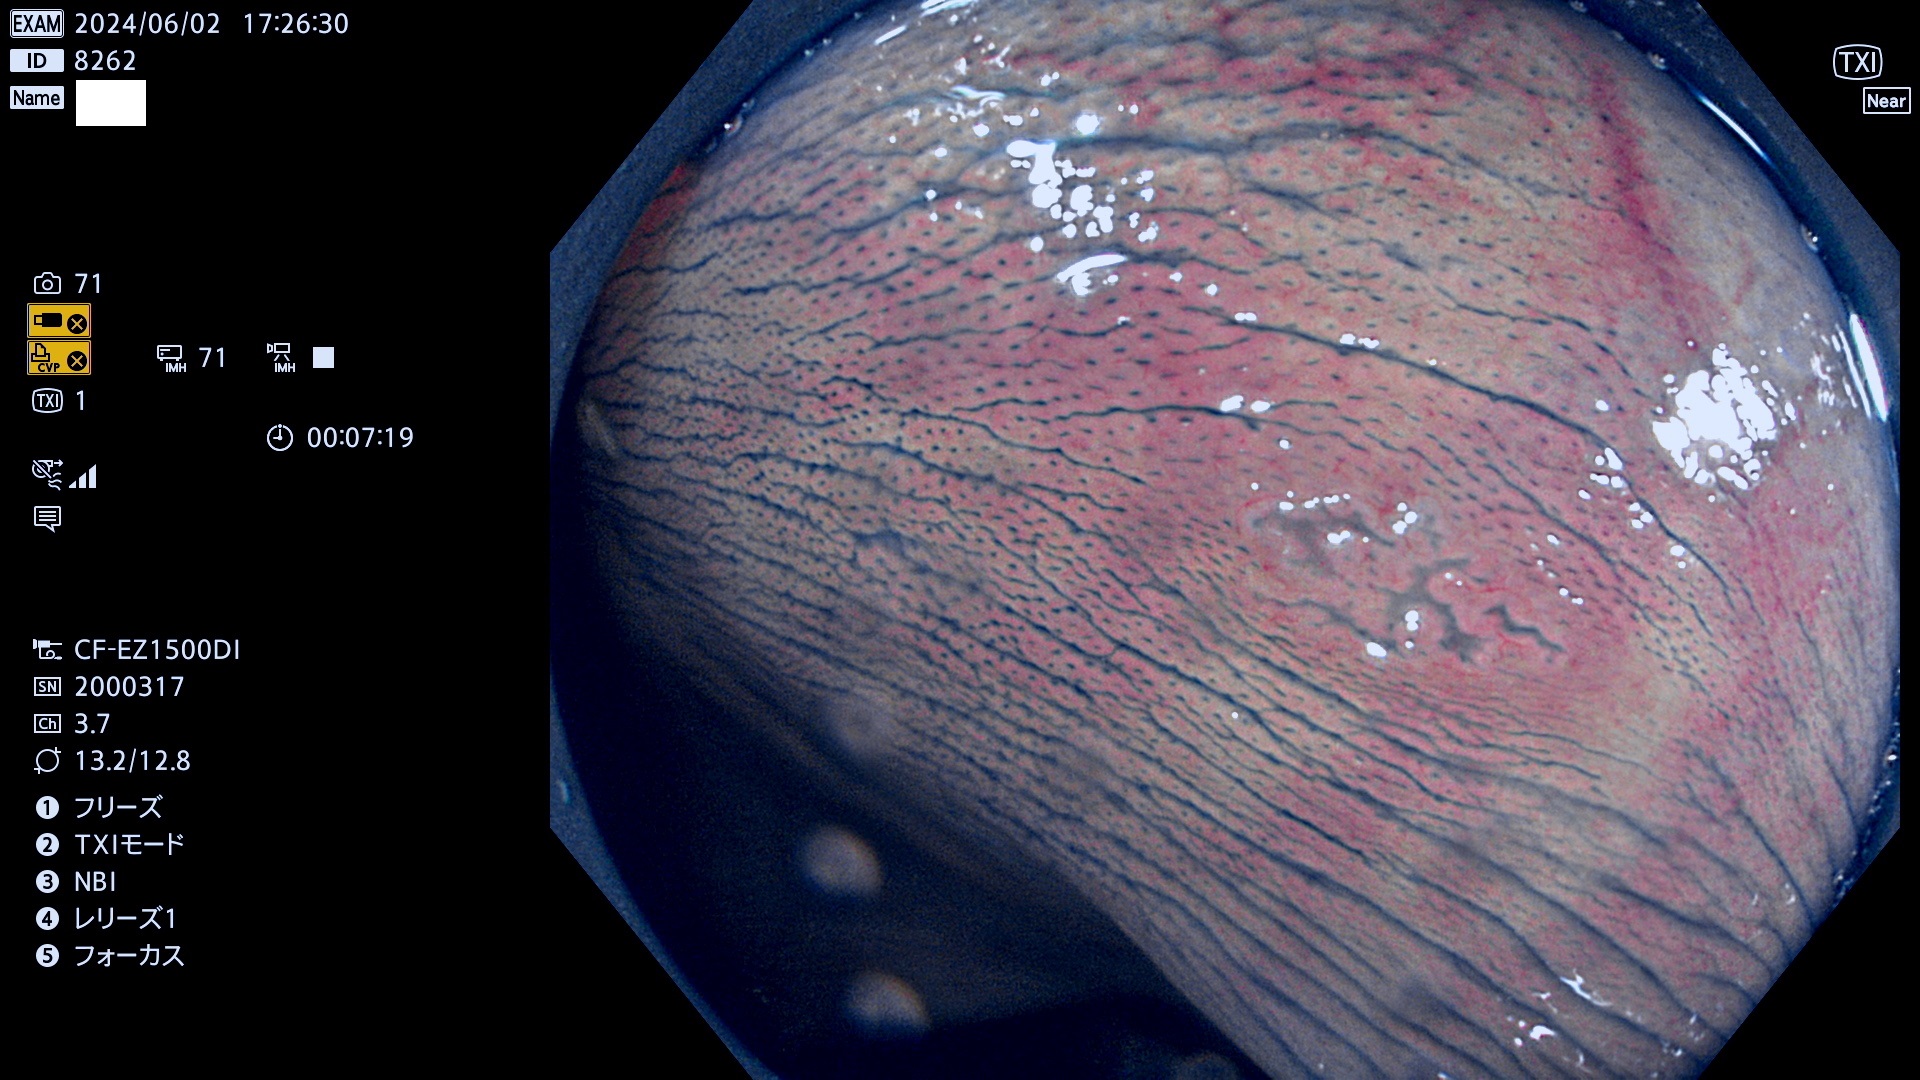

今週のUb、Uc型腺腫

表面型腺腫(Flat Adenoma)の中で、完全に平坦な物をUb、陥凹している物をUcと呼びます。平坦隆起型(Ua)よりも、発見が難しく危険な病変です。

毎週の検査(木・金・土・日)に発見されたUb、Uc型・腺腫を、その週の日曜の夜にUPし1週間、提示します。

抽出の対象期間 2024年5月30日〜6月2の4日間(40件の検査)7件 (7/40=18%)